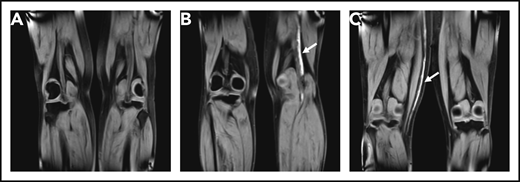

A total of 111 patients (36%) had a MRDTI positive for DVT, of whom 99 were not receiving anticoagulant treatment at the time of inclusion in the study and started anticoagulant treatment (Figure 2). Twelve patients were on anticoagulants at the time of study inclusion, and their treatment was modified after diagnosis. Thus, the overall prevalence of recurrent DVT at baseline, including 111 patients with MRDTI positive for DVT and the above-mentioned 5 patients with recurrent VTE diagnosed otherwise, was 38% (116 of 305). The baseline prevalence of recurrent DVT in patients on anticoagulants at inclusion was 21% (14 of 68; Figure 2). Figure 3 and supplemental Videos 1-6 show examples of MRDTI images and movies of 3 patients in which clear high signal intensities were seen in cases of acute thrombus and symmetrical low signal intensity in the absence of an acute thrombus.

Coronal MRDTI images from 3 study patients. (A) MRDTI negative for DVT with symmetric low signal intensity in both popliteal veins, despite an incompressible popliteal vein in the left leg upon CUS. (B) Asymmetrical high signal intensity in the left popliteal vein diagnostic of acute recurrent DVT of the left leg (arrow). (C) Asymmetrical high signal intensity in the right great saphenous vein diagnostic for acute thrombophlebitis, but not DVT, in the right leg (arrow).